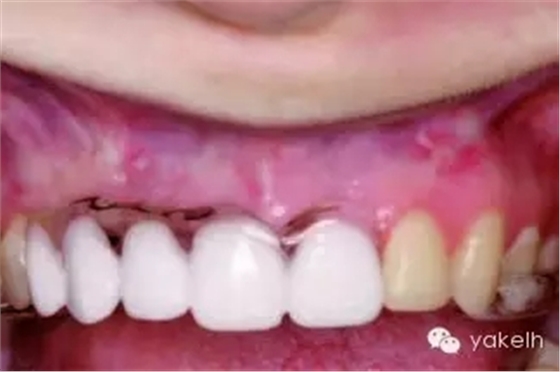

¤¤與口腔頜面部的其他供區(qū)相比,頦部術(shù)后并發(fā)癥的發(fā)生率更高。當(dāng)骨塊以及環(huán)形骨塊移除后,下前牙感覺異常是術(shù)后常見并發(fā)癥。如切牙管神經(jīng)在取骨過程中受損(圖13.24,圖13.25),患者會(huì)感到切牙感覺異常,該損傷通常在6個(gè)月內(nèi)可以自行修復(fù),此時(shí)前牙通常不需要做根管治療。但也會(huì)發(fā)生由于牙髓受損,導(dǎo)致下切牙變色或者繼發(fā)性牙本質(zhì)形成(圖13.26)。即使于前庭溝處做切口,也可出現(xiàn)頦部神經(jīng)感覺異常。骨移植患者發(fā)生頦神經(jīng)感覺異常的幾率較低,但是也有高達(dá)43%的并發(fā)癥發(fā)生率報(bào)道(13.27)。在寒冷的天氣時(shí),頦部氣候功能癥也有報(bào)道。盡管大多數(shù)受損的患者可恢復(fù)正常,但是仍給患者造成困擾。術(shù)前討論可能的并發(fā)癥是明智的,這包括手術(shù)會(huì)導(dǎo)致牙齒以及頦部感覺的異常。盡管未有術(shù)后頦部軟組織外形改變的報(bào)道,但患者往往擔(dān)心該區(qū)域取骨后是否會(huì)影響美觀。影像學(xué)證據(jù)表明,在一些老年患者中,供區(qū)骨空腔不能完全修復(fù)。用可吸收的骨替代品,如骨庫骨或者小牛骨充填供區(qū)的缺損,可以減少患者的疑慮。術(shù)后沒有發(fā)生過頦部下垂,但為防止頦部下垂,在取骨時(shí)應(yīng)避免把下頜骨上的組織完全撕脫。曾有報(bào)道在取骨后,下頜骨剩余舌側(cè)骨板發(fā)生骨折。如前所述,這可能是取骨時(shí),太靠近下頜骨邊緣所造成的。頦部取骨的術(shù)后疼痛比較明顯。術(shù)后應(yīng)用長(zhǎng)效局麻藥,如布比卡因行下頜神經(jīng)阻滯麻醉,可以延遲疼痛的發(fā)生,以便人體有充分的時(shí)間來吸收止痛藥。術(shù)前應(yīng)用非甾體類藥物,如布洛芬等可減少疼痛和腫脹。

圖13.27 頦部取骨后的神經(jīng)感覺減退。